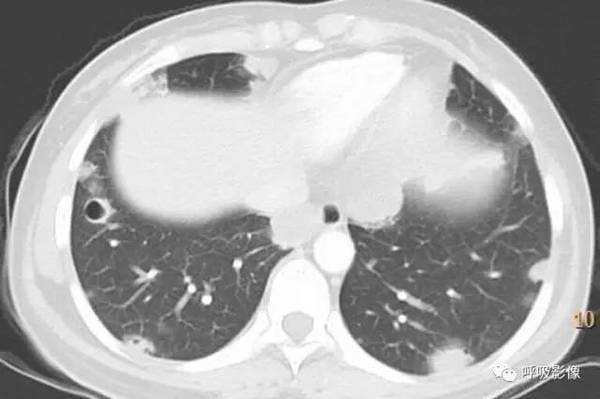

简单病史:女,43岁。咯血10余天。既往有子宫肌瘤切除病史。于山东省肿瘤医院查体,CT示:1.右侧附件区囊实性占位,同侧卵巢静脉显著增粗,考虑恶性肿瘤。2.双肺结节,考虑转移。3.宫体低密度灶,不除外子宫肌瘤。4.腹部、颈部扫描未见异常。子宫肌瘤病理切片会诊:子宫平滑肌瘤。盆腔附件包块穿刺活检细胞学检查示:查到可疑癌细胞。组织病理示:查见极少肿瘤细胞,考虑癌细胞。行紫杉醇联合卡铂化疗一疗程。

胸部CT示双肺多发结节影,强化明显,内见明显坏死,提示血供丰富。

转移瘤多具有原发肿瘤特点,本例转移瘤为生殖源性肿瘤,盆腔附件包块穿刺活检细胞学检病理均查见恶性肿瘤细胞,结合转移灶坏死、强化明显,需考虑绒毛膜癌缠医可能。

胸部CT双肺多发结节影,强化明显,内见明显坏死,提示血供丰富,这是诊断关键。